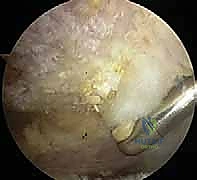

يتم إدخال كاميرا المنظار (Arthroscope) عالية الدقة (يستخدم د. هطيف تقنية 4K) من خلال ثقب خلفي صغير. يتم فحص المفصل الحقاني العضدي (Glenohumeral joint) بالكامل للتأكد من عدم وجود إصابات أخرى مرافقة، مثل تمزقات شفا المفصل (SLAP tears) أو التهاب وتر ذات الرأسين.

الخطوة الثانية: إزالة الكيس الزلالي الملتهب (Bursectomy)

يتم توجيه المنظار إلى الحيز تحت الأخرم (Subacromial space). غالباً ما يكون هذا الحيز مليئاً بالأنسجة الالتهابية والكيس الزلالي المتضخم الذي يعيق الرؤية ويسبب الألم. باستخدام أداة دقيقة تسمى "الشاڤر" (Shaver) وجهاز التردد الحراري (Radiofrequency wand)، يتم تنظيف وإزالة هذا النسيج الملتهب بالكامل لكشف السطح السفلي لعظم الأخرم وأوتار الكفة المدورة.

الخطوة الثالثة: تجميل الأخرم وتوسيع المساحة (Acromioplasty)

هذه هي الخطوة المحورية. بمجرد كشف العظم، يتم تقييم النتوءات العظمية (Spurs) وشكل الأخرم المعقوف. باستخدام أداة كشط عظمية دوارة دقيقة (Burr)، يقوم الجراح بنحت السطح السفلي لعظم الأخرم، وإزالة النتوءات العظمية، وتحويل الأخرم من الشكل المعقوف (النوع 3) إلى الشكل المسطح (النوع 1).

يتم أيضاً تحرير أو قطع جزء من الرباط الغرابي الأخرمي (CA ligament) إذا كان متصلباً ويساهم في الضغط. النتيجة النهائية هي مساحة واسعة ومسطحة تسمح لأوتار الكتف بالانزلاق بحرية تامة دون أي احتكاك.